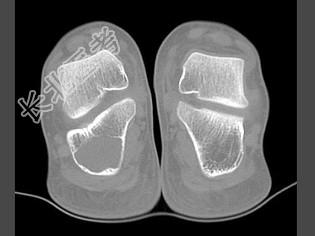

- 单项选择题女,15岁, 间歇性足跟痛,结合图像, 最可能的诊断是 ( )

A、骨囊肿

B、骨巨细胞瘤

C、骨髓瘤

D、骨纤维异常增殖症

E、动脉瘤样骨囊肿